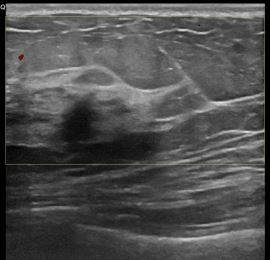

상기환자는 외부검사이상소견으로  내원하신 40대후반

여성분으로 의심스러운 좌측혹 조직검사 시행해 침윤성암 으로 진단되었습니다